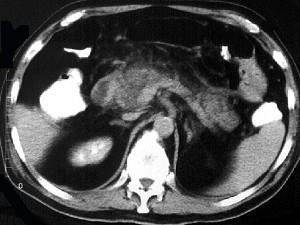

问题 男,32岁,上腹部持续性疼痛,放射至胸背部,高热,恶心呕吐,上腹部压痛反跳痛,CT检查如图,最佳的诊断是 ( )

选项 A、慢性胰腺炎急性发作 B、胰腺癌 C、出血坏死性胰腺炎 D、慢性胰腺炎 E、急性单纯性胰腺炎

答案 C